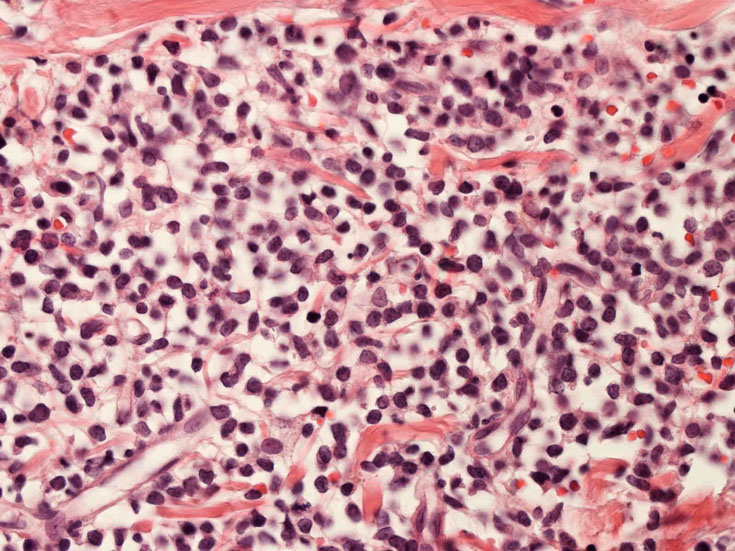

罹患リンパ節の基本構造は消失し腫瘍細胞のびまん性増殖で置換されている。非腫瘍性の小リンパ球(CD3+, CD4/8+)が濾胞様に散在して残る(Fig.01)。不整型または類円形の明るい核をもつmedium-sizeのリンパ球様細胞が密に増殖している。細胞質は乏しい(Fig.02)。CD68陽性macrophageが多く混在する部分が認められた(Fig.03)。

residualfollicle01.jpg

tcells01.jpg

tandm01.jpg

Fig.01Fig.02Fig.03